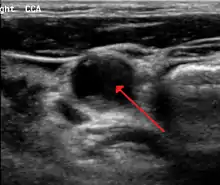

70 percent stenosis of the right internal carotid artery as seen by ultrasound. Arrow marks the lumen of the artery.

Carotid artery stenosis is usually diagnosed by color flow duplex ultrasound scan of the carotid arteries in the neck. This involves no radiation, no needles and no contrast agents that may cause allergic reactions. This test has good sensitivity and specificity.[16]

Typically duplex ultrasound scan is the only investigation required for decision making in carotid stenosis as it is widely available and rapidly performed. However, further imaging can be required if the stenosis is not near the bifurcation of the carotid artery.[17]

One of several different imaging modalities, such as a computed tomography angiogram (CTA)[18][19][20] or magnetic resonance angiogram (MRA) may be useful. Each imaging modality has its advantages and disadvantages - Magnetic resonance angiography and CT angiography with contrast is contraindicated in patients with chronic kidney disease, catheter angiography has a 0.5% to 1.0% risk of stroke, MI, arterial injury or retroperitoneal bleeding. The investigation chosen will depend on the clinical question and the imaging expertise, experience and equipment available.[21]